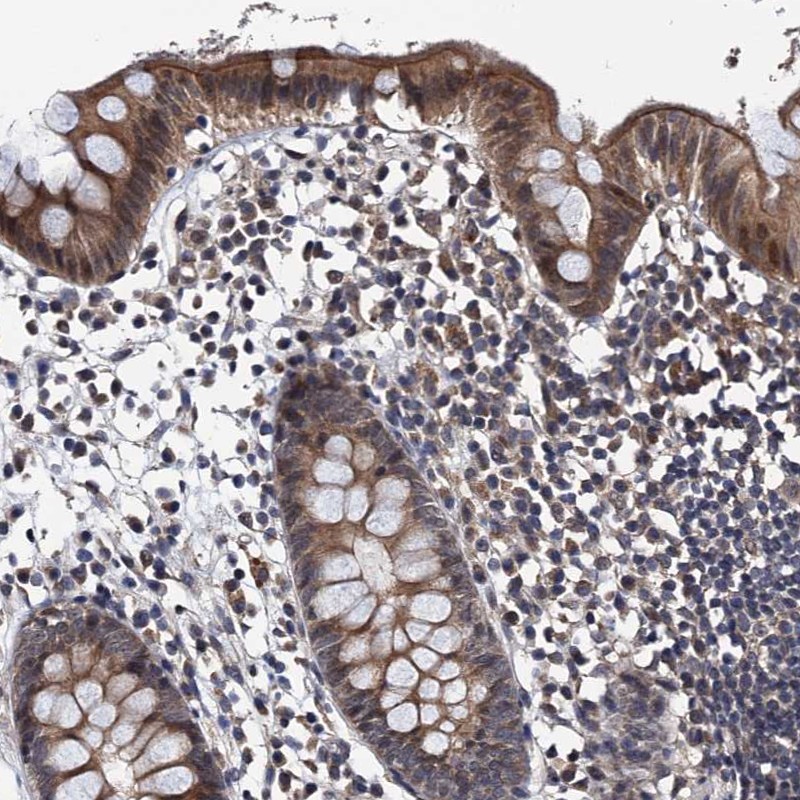

Immunohistochemical staining of human appendix shows moderate cytoplasmic positivity in glandular cells.